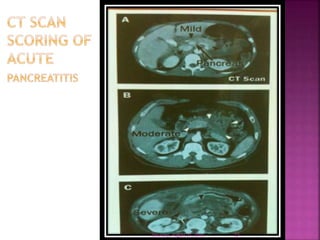

4. CT scan (most preferred)